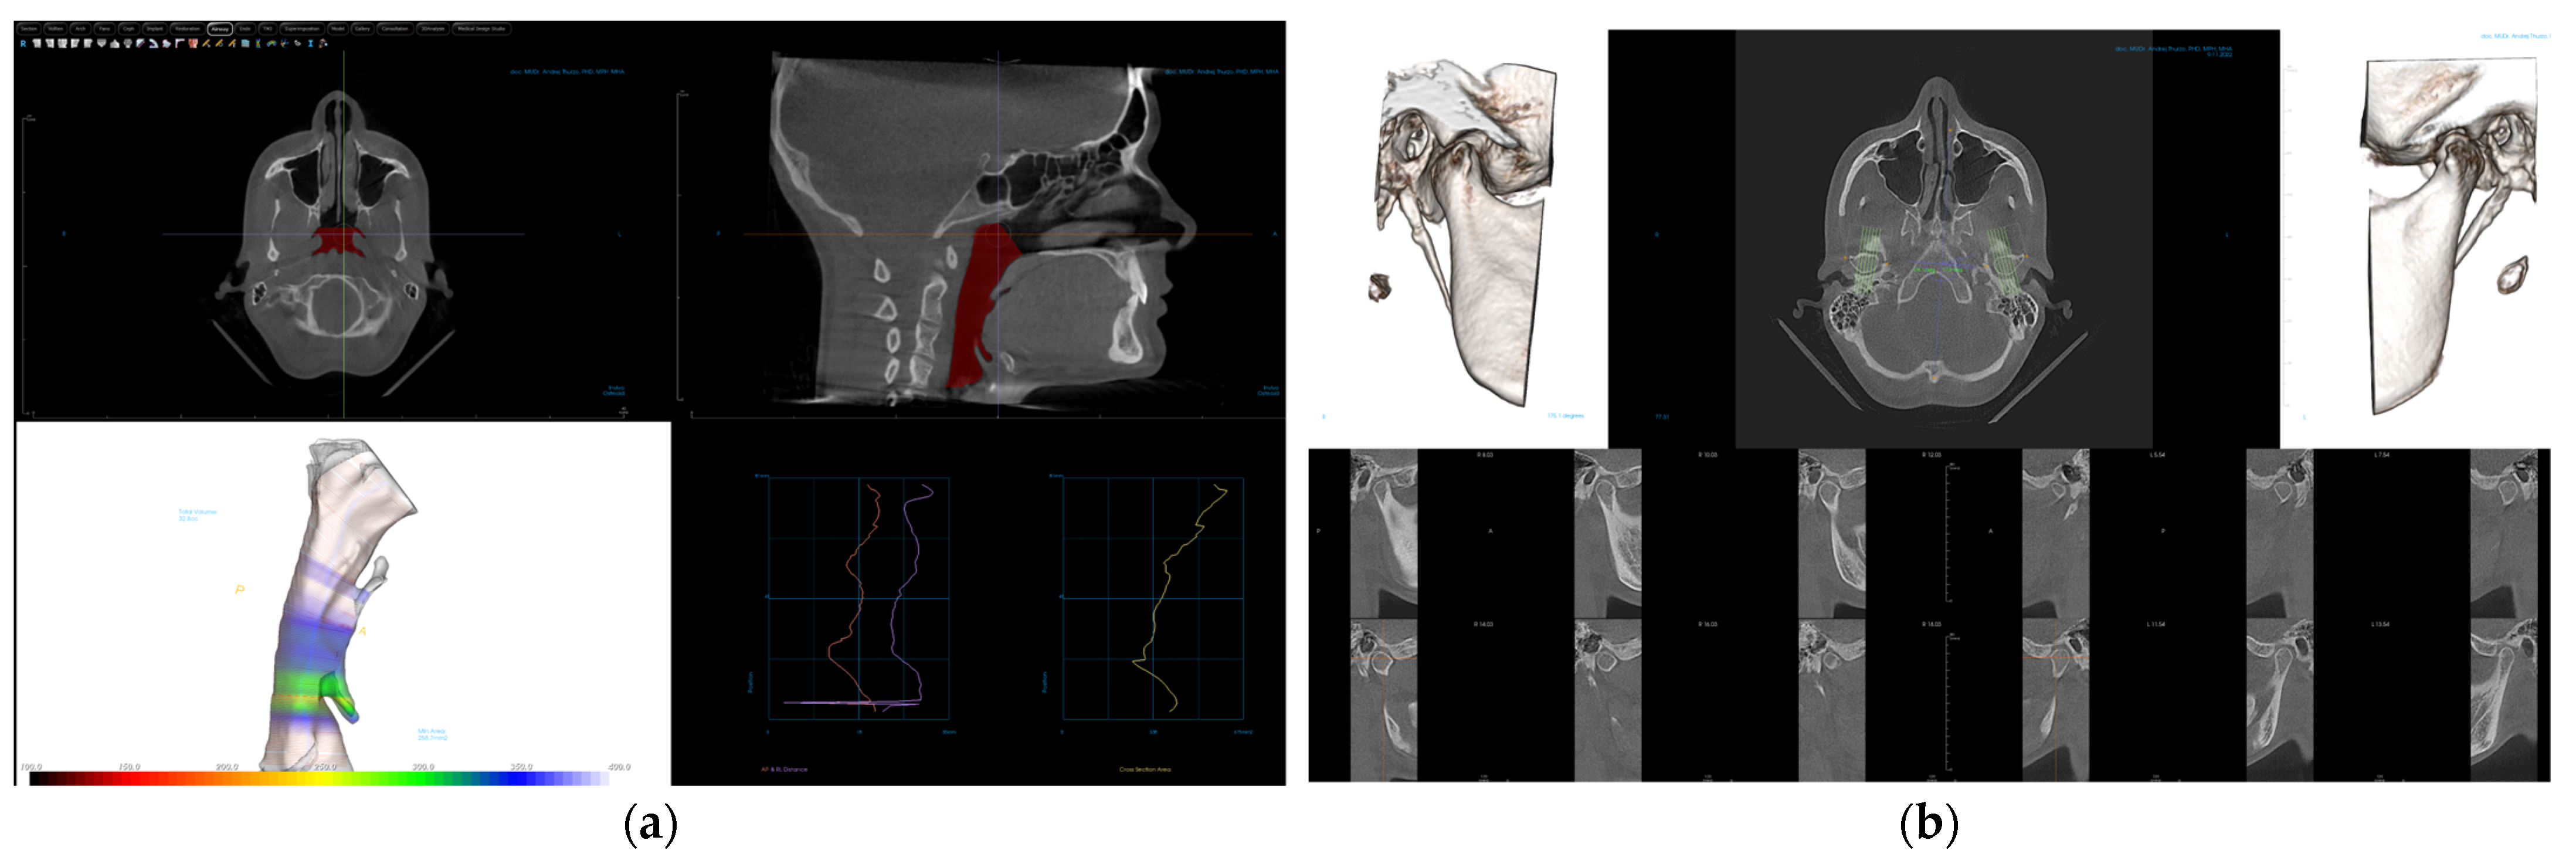

- Diagnocat (USA—Diagnocat LTD, Miami, FL, USA) for AI segmentation;

- Invivo 7.0 (Anatomage, Santa Clara, CA, USA) for segmented model analysis;

2.3. Processing CBCT